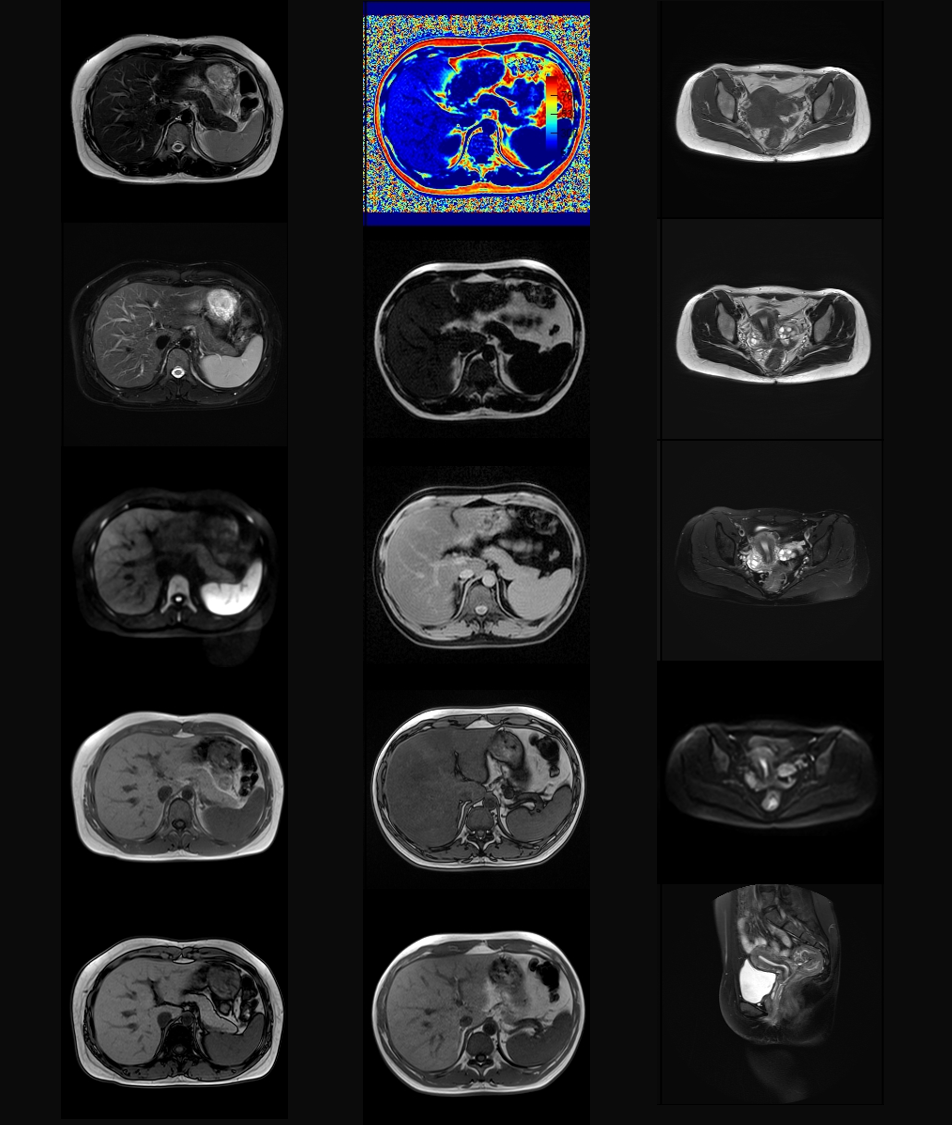

¸¹²¿&ÅèÇ»